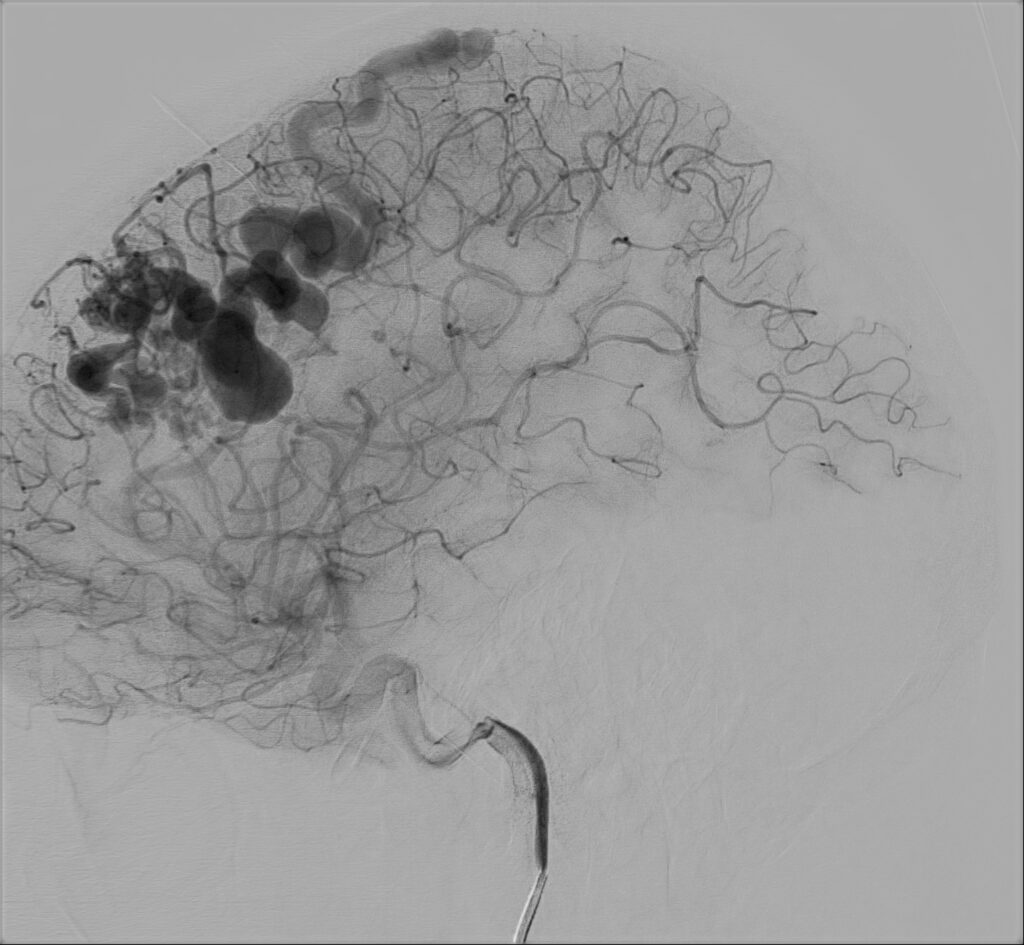

47-letnia kobieta z wywiadem krwotoku z malformacji tętniczo-żylnej (AVM) w prawej okolicy czołowej kilka lat temu, po kilkukrotnej embolizacji zmiany, zarówno w Polsce, jak i w Holandii, została przyjęta do Oddziału z powodu drugiego w życiu krwotoku ze zmiany naczyniowej.

W badaniu CT widoczne jest rozległe krwawienie dokomorowe.

W badaniu angiografii subtrakcyjnej widoczne jest rozległe (ponad 3 cm) gniazdo naczyniowe zaopatrywane z tętnicy przedniej mózgu prawej, zarówno z gałęzi okołospoidołowej, która oddawała 2 tętnice żywiące, jak i gałęzi korowych, oddając jedno naczynie żylne drenujące do zatoki strzałkowej górnej.

W tym przypadku chora została zakwalifikowana do leczenia operacyjnego – kraniotomii czołowej przystrzałkowej i resekcji zmiany naczyniowej. Zmiana została usunięta, bez nowych deficytów neurologicznych. W kontrolnym badaniu DSA nie uwidoczniono resztkowej przetoki naczyniowej, co jest sukcesem operacyjnym.